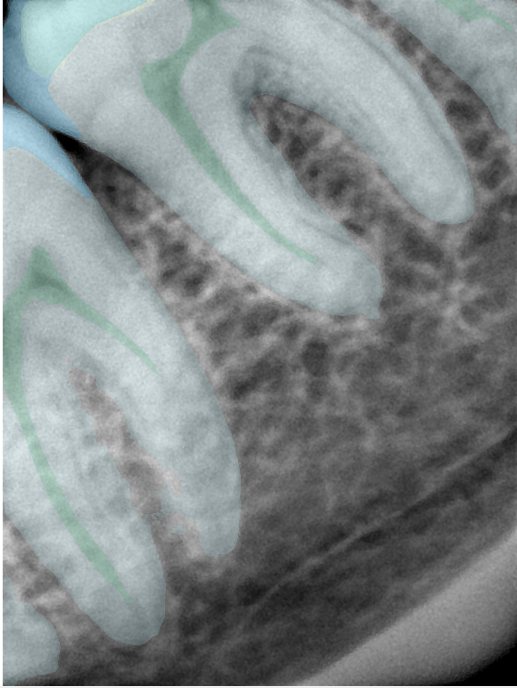

CR/DR 牙齿分割阶段记录

当前进展

- 完成了 CR/DR 牙齿相关分割训练

- 当前结果已经达到阶段预期,但仍有细节问题需要继续处理

相关测试

遇到的问题

- 训练过程中出现过 mask 下移问题

- 部分结果会出现 box 填充异常

- mask 边缘仍然有比较明显的锯齿感

参考

第二版算法问题测试